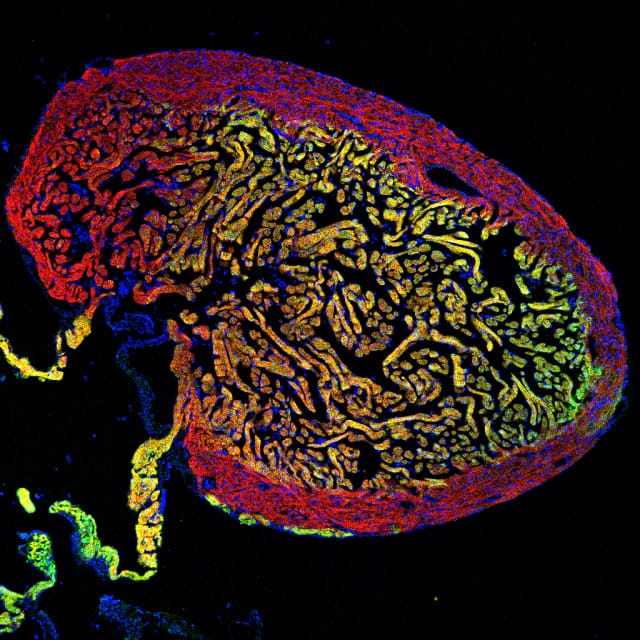

Bild: Institut für Anatomie, Universität Bern

Schnitt durch ein Zebrafischherz mit zwei unterschiedlichen Muskelzellschichten (gelb und rot). Die regenerierenden Zellen des gelben Bereichs können auch zum Wiederaufbau der roten Schicht beitragen.

Der Zebrafisch hat die erstaunliche Fähigkeit, sein Herz sogar nach schwerwiegenden Schäden wieder zu regenerieren. Dabei teilen sich Herzmuskelzellen, um das zerstörte Gewebe zu ersetzen. Da dieser Prozess im menschlichen Herzen nicht vorhanden ist, suchen Wissenschaftler nach den Mechanismen, die ihn im Zebrafisch auslösen.

Die regenerierenden Herzmuskelzellen können sich im ausgewachsenen Herzen anpassen, um den Zellen in den verschiedenen Regionen der vormals defekten Herzwand zu ähneln. Es zeigte sich auch, dass Herzmuskelzellen aus allen Teilen des Herzens bei der Reparatur helfen.